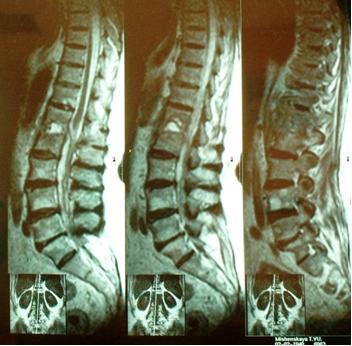

- МРТ (магнитно-резонансная томография) – метод выбора, обязателен при диагностике спондилодисцита, остеомиелита позвоночника и дисцита, демонстрирует вовлечение дискового пространства и тела позвонка, позволяет исключит паравертебральный или эпидуральный спинальный абсцессы, малоинформативна для определения сращения костей;

Преимуществом МРТ исследования при остеомиелите позвоночника является высокая специфичность (93 %) и чувствительность (96 %).

Для лучшей визуализации паравертебральных и эпидуральных абсцессов при МРТ исследовании используется введение контрастного вещества - гадолиниума.

Для уточнения диагноза назначают инструментальное обследование, которое включает рентгенографию и магнитно-резонансную томографию (МРТ). Последняя имеет большую информативность, выявляет дефекты костного мозга и межпозвоночных дисков на ранних этапах патологии, когда изменения не визуализируются при рентгенологическом исследовании. На рентгенограмме и томограмме определяют неровность краев тел позвонков, узурацию, сужение межпозвоночных дисков, блок пораженных участков позвоночного столба. При проведении люмбальной пункции выявляется помутнение спинномозговой жидкости, увеличение количества белка, большое содержание лейкоцитов, примесь гноя.